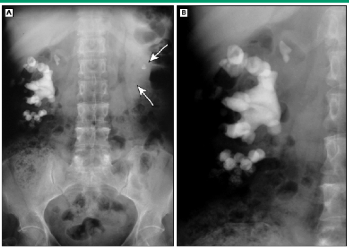

nephrolathiasis

struvite stone

what 2 things is this associated with?

4 bacteria?

can you pass them?

when do they get bigger?

3 tx options?

“staghorn” stones that always associated with UTI and alkaline urine

Tx: